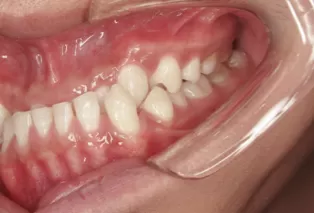

Male, 23 years old. Chief complaint: suffered from underbite for over 10 years.

Treatment outcome: straightened teeth, good occlusion, improved profile and smile.

Intraoral photos